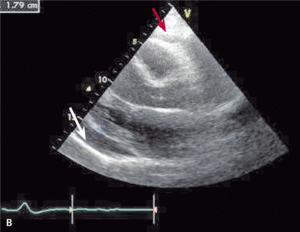

U chorych z płynem w worku osierdziowym obserwujemy mały woltaż załamków w EKG (ryc. 1), szczególnie charakterystyczny dla dużych wysięków lub tamponady. Niekiedy stwierdza się obniżenie odcinka PQ i zmiany ST-T. Tamponadzie towarzyszy zwykle naprzemienność elektryczna, która na ogół wiąże się z obecnością dużej ilości płynu [10].